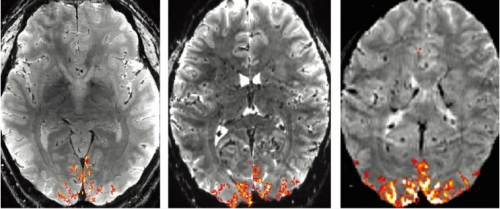

NexGen 7T fMR(左)内有一个7特斯拉超导电磁铁。该机器的分辨率高于标准的3T医院扫描仪右)和传统7T成像仪(中)

其总体效果是空间分辨率达到了广泛使用的fMRI仪器的50多倍,超过其他7T fMRI一个数量级。在某些情况下,体素从约1微升(1立方毫米)缩小到不到0.1微升,相当于较粗的沙子大小。